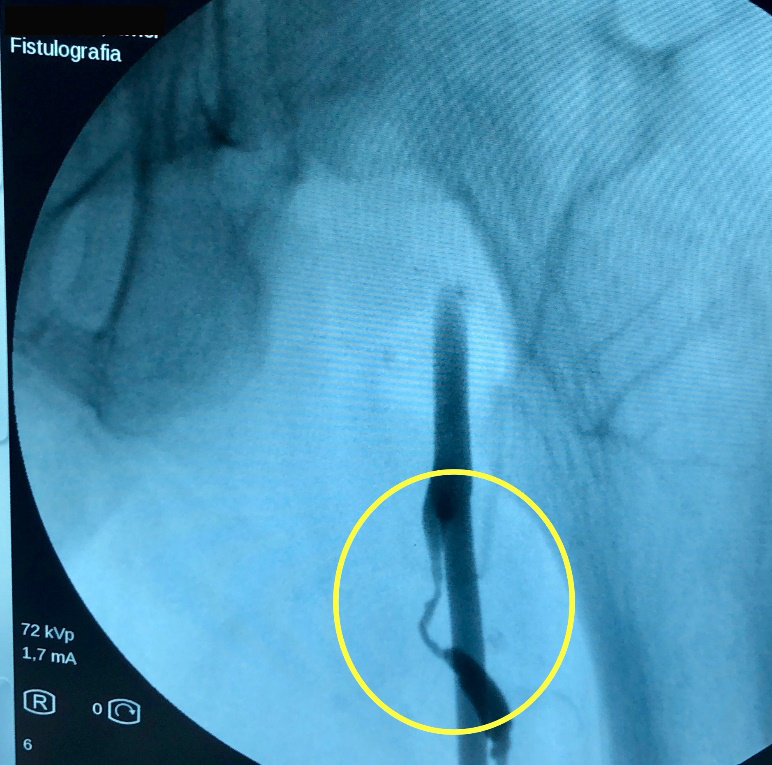

Se realizó ecodoppler, el cual informó permeabilidad del acceso vascular con aumento del espesor de la pared de la vena proximal a la arteria. Debido a la semiología, doppler y dinámica de la diálisis, se decidió ingresarla a quirófano a fin de realizar angiografía diagnóstica y, eventualmente, terapéutica. Durante el procedimiento se constató estenosis suboclusiva severa y extensa con repercusión hemodinámica, próxima a la anastomosis arterial, por lo que se decidió reparación endovascular con angioplastia con balón con droga de la FAV safeno-femoral en loop. (Imagen 3 . 4)

Se realizó abordaje del tercio medio de la fístula, con anestesia local y sedación anestésica, bajo control radioscópico con Arco en C Philips Pulsera®. Se realizó punción retrógrada de vena safena, por visión directa con introductor de 5 Fr, se progresó con cuerda hidrofílica de 0.035x260 atravesando lesión obstructiva hacia la arteria femoral común (Imagen 3).

Se realizó una primera dilatación con balón simple de 5 x 60, durante 120 segundos continuos a 8 ATM. Control angiográfico: constató dilatación con pequeño flap de disección (Imagen 4). Se procedió a realizar angioplastía con balón con Paclitaxcel de 6 x 60 RANGER®, durante 180 segundos a 6 ATM, obteniendo resultado satisfactorio con buen flujo en el recorrido completo de todo el acceso sin necesidad de colocar stent.